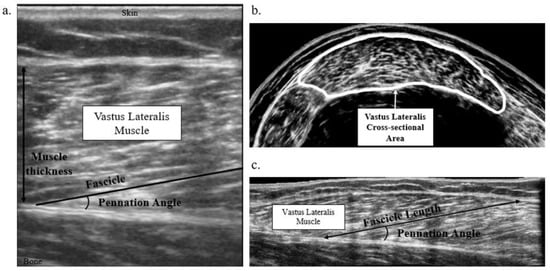

2.2. Muscle Macrostructure